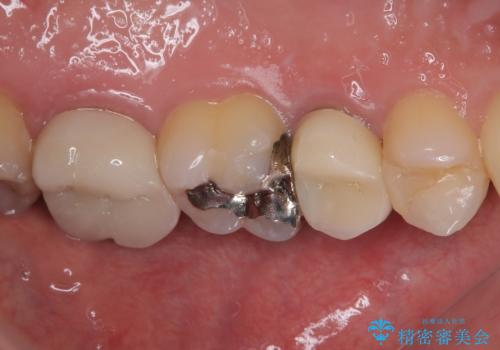

見た目、機能面ともに満足していただけました。

今後もメンテナンスで通っていただきながら、経過観察していく予定です。